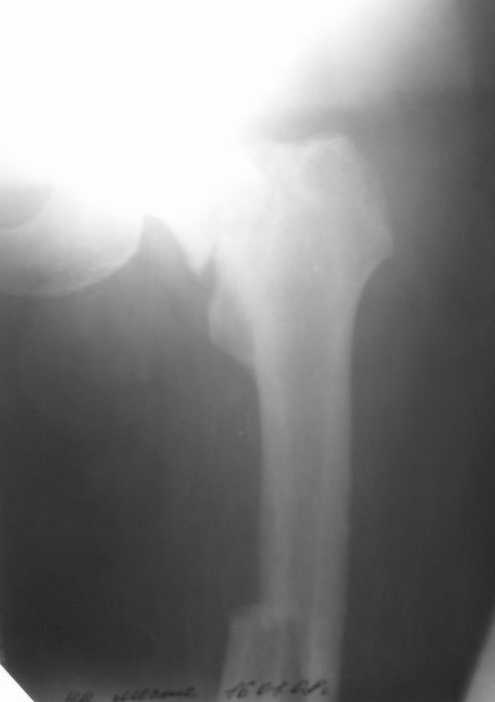

Уважаемые коллеги! Поступил пациент 46 лет после автоаварии от 3.01.

Лечился в ЦРБ. К нам поступил вчера. Имеется оскольчатый перелом диафиза левого бедра, перелом медиального мыщелка, краевой перелом надколенника. У нас, кроме того, выявили перелом шейки бедра. Перелом закрытый, имеется рана в в/3 голени(ниже уровня бугристости б/берцовой кости)без признаков инфицирования.Планируем закрыто фиксировать мыщелок и надколенник винтами, затем закрыто заштифтовать бедро. Вопрос возник по перелому шейки: что предпочесть - длинный PFN или DFN + DHS на шейку?Буду благодарен за ценные советы.С уважением, Станислав Дмитриев.

Заранее приношу извинения за качество снимков. То что есть - либо из ЦРБ, либо сделано в приемном покое, где дежурят рентгенлаборанты различной квалификации. Завтра постараемся сделать снимки всего бедра на длинные кассеты в 2 проекциях. Сейчас больной на скелетном вытяжении. Состояние стабильное.